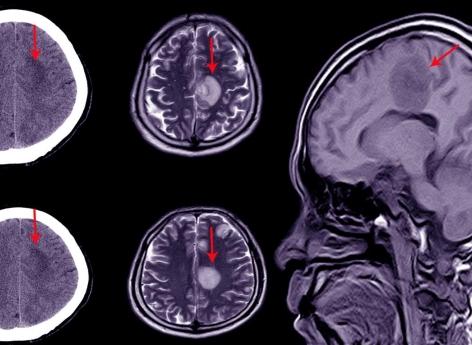

L’hématome sous-dural est généralement consécutif à un choc au crâne (accident, coup, bébé secoué...) ayant provoqué la lésion d’une veine, à l’origine du saignement. Le diagnostic est posé grâce à un scanner ou une IRM cérébrale. Si les petits hématomes ont tendance à se résorber spontanément, les plus importants nécessitent une intervention chirurgicale. En l’occurrence un drainage, qui consiste à percer un trou dans la boîte crânienne pour évacuer l’hématome.

Le pronostic vital de l’hématome sous-dural chronique est plutôt bon, mais le taux de mortalité en cas d’hématome aigu est "d’environ 30 % si le patient est opéré dans les 4 heures qui suivent le choc" et "au-delà, il peut atteindre 90 %", affirme le neurochirurgien Marc Guénot auprès du Journal des femmes.